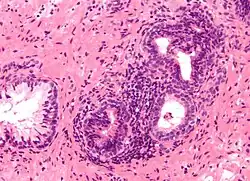

| Micrograph showing an inflamed prostate gland, the histologic correlate of prostatitis. A normal non-inflamed prostatic gland is seen on the left of the image. H&E stain. | |